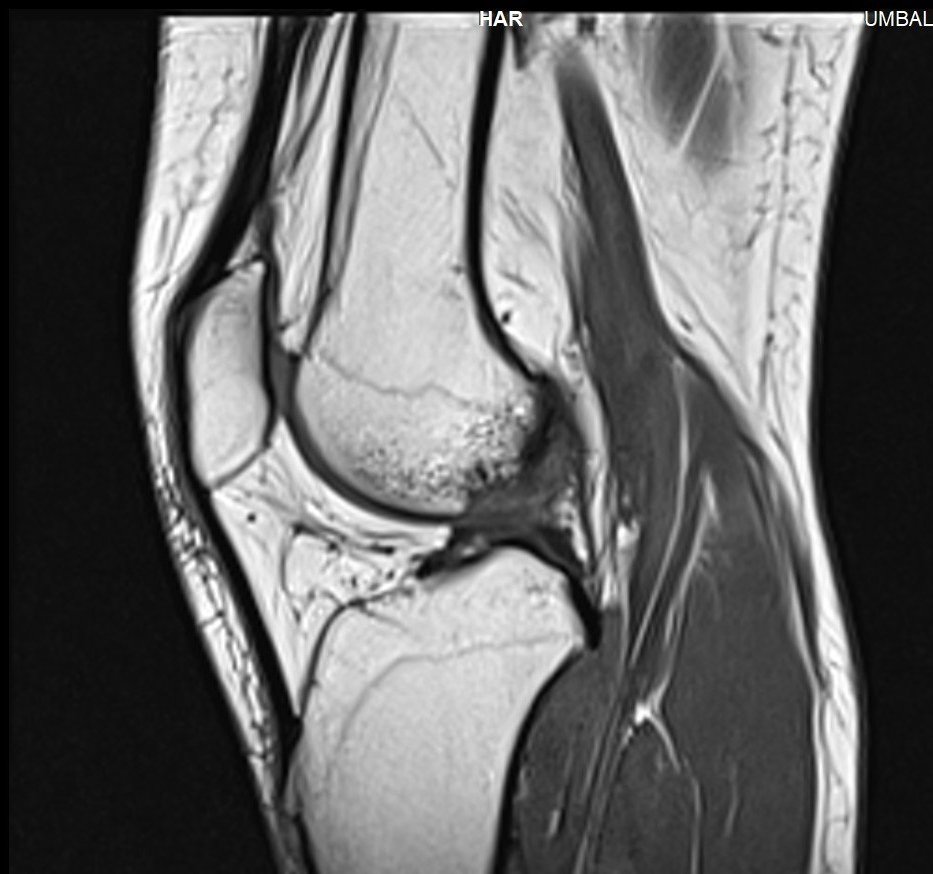

Здравейте, тъй като незнам как да ви кача целия диск Ви качвам малко снимки

Здравейте, благодаря за ЯМР-а.

Подборът на срезове/снимки не е най- добрият. Моля да изпратите диска на имейл: infо@beta-clinic.com или чрез спедитор на адреса на Бета клиник.